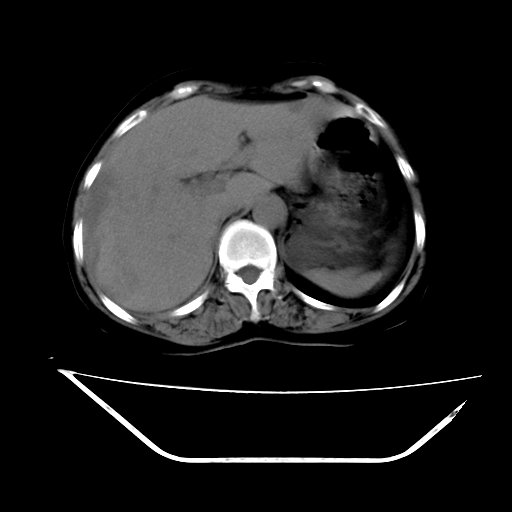

ct增强

考虑肝腺瘤出血可能,肝血管瘤增强表现不是很典型,放在第二。

6月份ct片显示肝内巨大混杂密度团块,伴包膜下积液(内含液液平面),增强多无明显强化。只能考虑肝占位病变,并肝内、血膜下血肿。肝ca并出血多见,而肝血管瘤并破裂出血少见。

从平扫+增强及治疗后复查片,病变明显缩小,不考虑肝癌出血可能,还是考虑为良性病变可能性大;单纯血肿并包膜下积液吧,病变强化没法解释,肝血管破裂出血吧,增强不符合典型血管瘤的表现,良性肿瘤破裂出血吧,复查片看来好像也不太支持(没做强化也不太好说)。本人还是考虑单纯肝内血肿并包膜下积液,强化是不是血管有外渗。